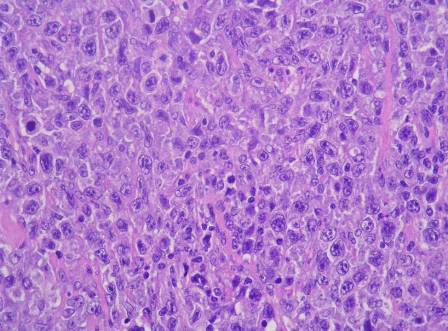

El diagnóstico se basa en la biopsia de ganglio linfático, que revela la presencia de células tumorales.

El examen inmunohistoquímico fenotípico, así como la evidencia de la expresión anormal de ciclina D1 (o de translocación t(11;14), por FISH o citogenética clásica) son necesarios para confirmar el diagnóstico. La evaluación de la extensión de la enfermedad se realiza mediante técnicas de imagen (ecografía, escáner CT o RM), así como mediante análisis de la médula ósea (biopsia). Los exámenes endoscóspicos deben realizarse para detectar la afectación intestinal.